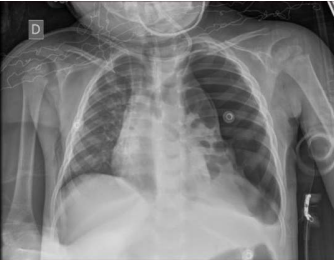

Uma paciente de dois anos de idade foi levada ao serviço de emergência com história de estar tratando uma pneumonia com cefalexina há quatro dias e, há um dia, vir apresentando piora do estado geral, prostração e inapetência. Ao exame, paciente em mau estado geral, agitada, toxemiada, afebril, com FC de 140 bpm, FR de 50 ipm, sat. de O2 de 85% em nebulização, PA de 80 x 45 mmHg, MV presente bilateralmente e diminuído à esquerda, tempo de enchimento capilar de 3 segundos e pulsos periféricos finos. Decidiu-se intubar a paciente e, durante a preparação do material e das drogas pela equipe da enfermagem, estabeleceu ventilação com bolsa-valva-máscara. Após alguns minutos, ainda antes do procedimento, a paciente iniciou crise de tosse, com FC de 180 bpm, FR de 65 ipm, sat. de O2 de 78% em ventilação com bolsa-valva-máscara e PA de 60 x 30 mmHg. A radiografia realizada na sala de emergência segue abaixo.